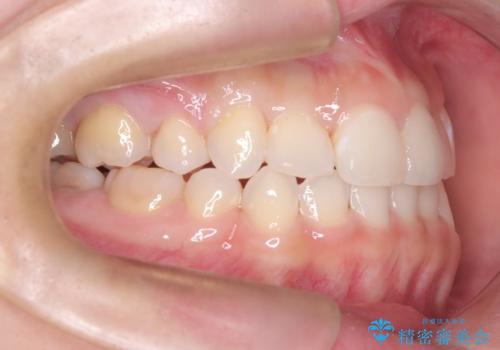

インビザラインによる精密な仕上げ: 全体のがたつきが概ね整った段階で、インビザライン(マウスピース矯正)へ移行しました。透明で目立たないマウスピースを使用しながら、0.1mm単位の細かな歯の配置や、最終的な咬み合わせのバランスを精密に整えていきました。

治療の結果、重度のがたつきは跡形もなく解消され、抜歯したスペースもきれいに閉じました。ワイヤーによる「確実な移動」と、インビザラインによる「緻密な仕上げ」を組み合わせることで、審美性と機能性の両立を叶えた美しい歯並びを実現しました。